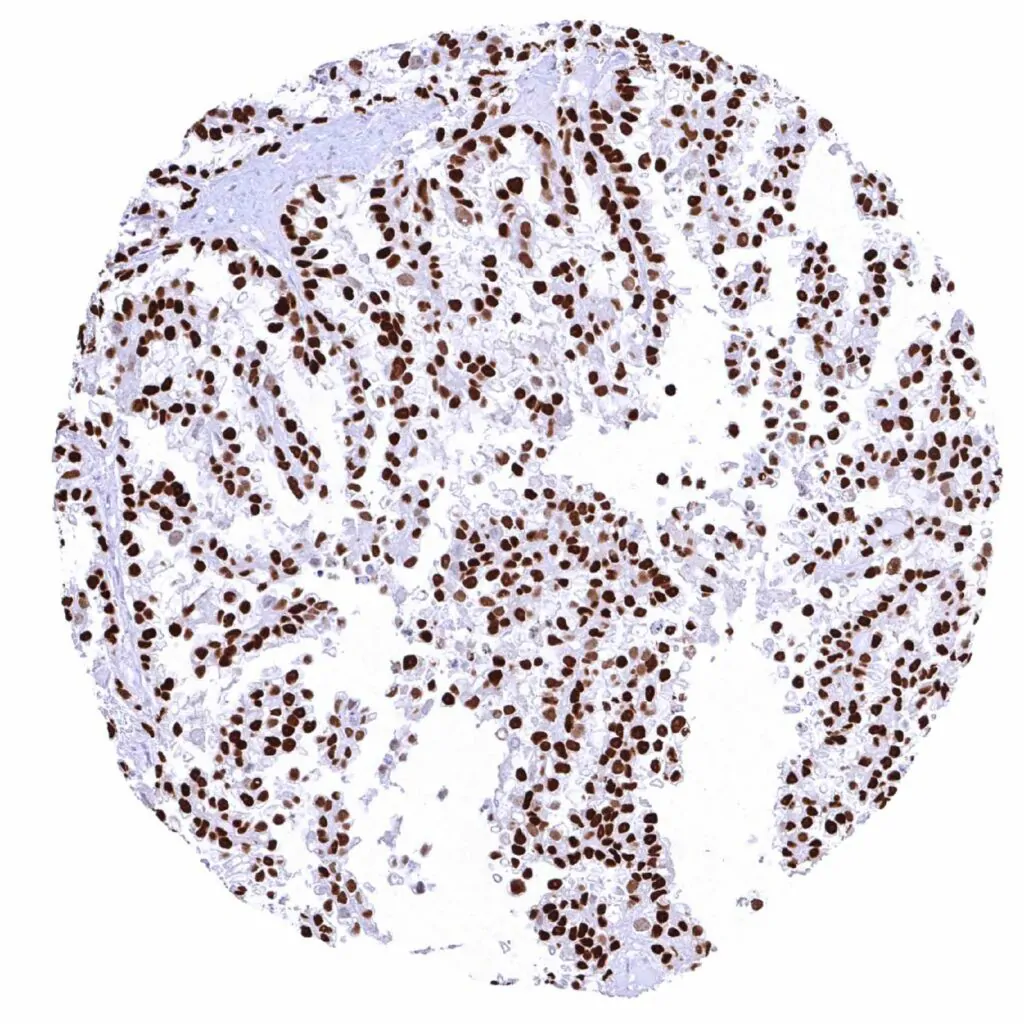

Urinary bladder – Muscle-invasive urothelial carcinoma (pT2-4) with a moderate to strong Cyclin E1 positivity of a large fraction of tumor cells